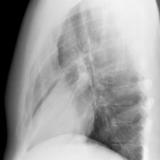

Case 1 Lateral

Date: 02/28/2004

Views: 3190